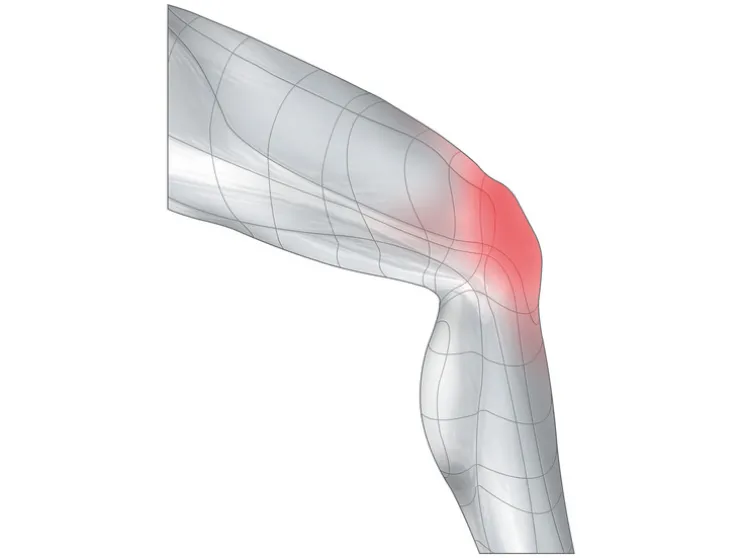

- Stabiliserende bandage voor de ondersteuning en ontlasting van het kniegewricht en de knieschijf

- Verwondingen aan het kniegewricht (zoals verrekkingen, verstuikingen en kneuzingen)

- Gewrichtspijn door slijtage (gonartrose)

- Beschadiging meniscus

- Milde gewrichtsinstabiliteit

- Overbelastingsblessures (“patellapeessyndroom”, “Ziekte van Osgood-Schlatter”)

- Knieschijfaandoeningen (patelladysplasie, na ontwrichting)

- Vermindert zwelling door milde compressie